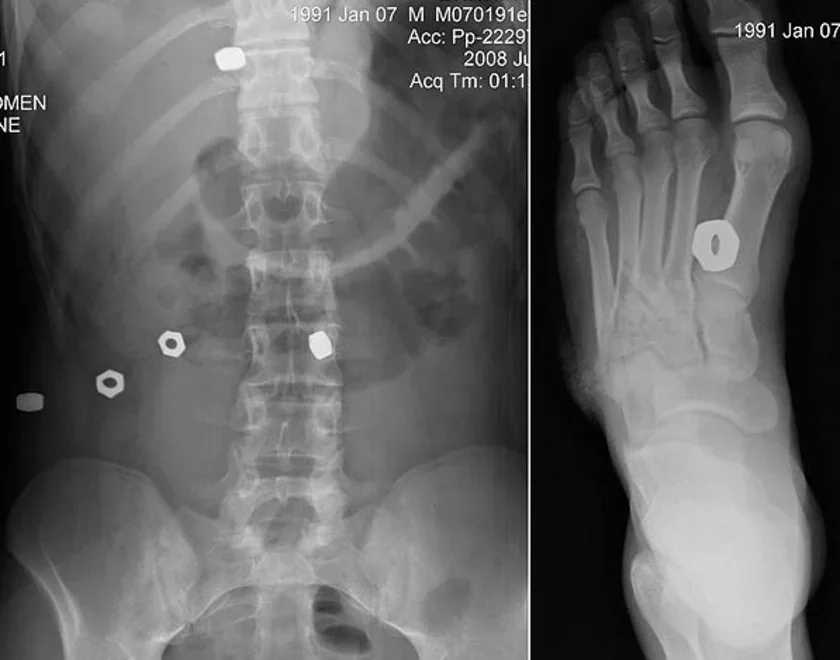

Да нас прывезьлі каля 20 чалавек, усе жывыя, раны розных памераў і цяжкасьці, у асноўным галёнак, зь іншароднымі целамі (гайкі), адзін адкрыты пералом галёнкі.

З пацярпелых, дастаўленых да нас у бальніцу, самым цяжкім аказаўся хлопчык 18-ці гадоў, якога нафаршыравала гэтымі жалязякамі больш за ўсіх: у ступні, перадплеччы, грудной і чэраўнай паражнінах. Яго ратаваць скончылі толькі а 9:00.